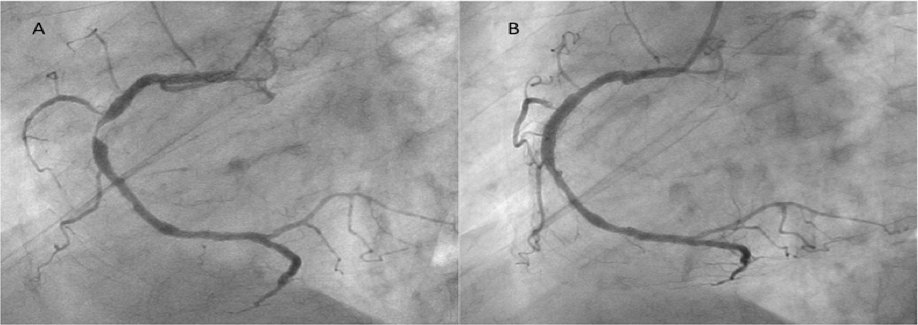

Figure 1. Angiographic images of a significant stenosis at the mid right coronary artery in case 1, (A) before and (B) after deployment of a 3.5 × 18 mm Nobori stent (click thumbnail to view larger image).

Right coronary angiography revealed an intact stent, with a new site of 90% stenosis in the middle of the RCA (Figure 1A). Intravascular ultrasound (IVUS) images revealed moderate superficial calcification around the target lesion; therefore, we performed pre-dilatation with a 2.5 × 12 mm non-slip element balloon, which effectively expanded the calcified lesion. A 3.5 × 18 mm Nobori stent was then deployed at 10 atm, followed by postdilatation up to 20 atm with a 3.5 × 10 mm non-compliant balloon. Final IVUS examination and angiography revealed an excellent result (Figure 1B), and the patient was discharged.